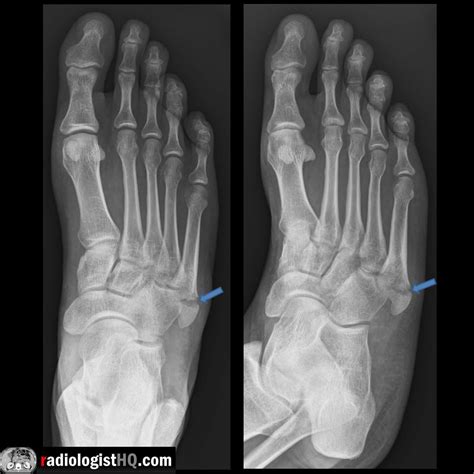

A Pseudo Jones Fracture is a specific type of fracture that occurs in the fifth metatarsal bone of the foot. This bone is located on the outer side of the foot and connects to the little toe. The term "Pseudo Jones" distinguishes it from a true Jones fracture, which occurs at the base of the fifth metatarsal. A Pseudo Jones Fracture typically involves a fracture at the proximal diaphysis of the fifth metatarsal, just distal to the tuberosity.

• Order X-rays to visualize the fracture and determine its location and severity.

Pseudo Jones Fracture Proximal diaphysis of the fifth metatarsal Sudden impact, twisting, or rolling the ankle Non-surgical (RICE, immobilization), Surgical (ORIF, bone grafting)

Jones Fracture Base of the fifth metatarsal Sudden impact, twisting, or rolling the ankle Non-surgical (RICE, immobilization), Surgical (ORIF, bone grafting)